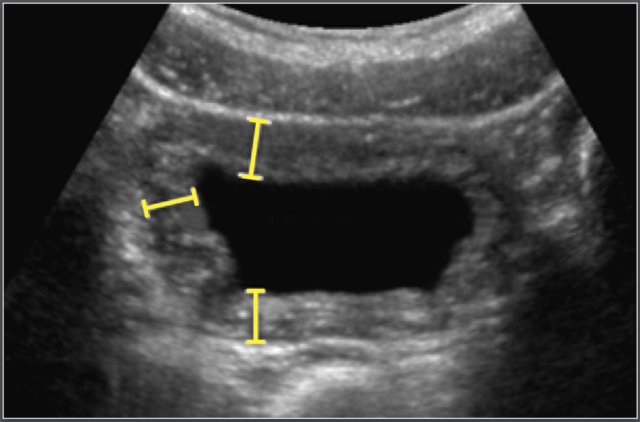

Bladder

Adapted from reference 17 Adapted from reference 17

Bladder volume

Material and method

A total of 3376 children were recruited in this ultrasonographic study.

The total number of patients does not add up to the total number of patients in this study because not all age-subgroups were included in the table.

The bladder volume was calculated first by measuring the maximum length (L) of the urinary bladder on the longitudinal scan, which was obtained from the neck to the fundus of the bladder.

Depth (D) was measured, perpendicular to the first plane at the level of the maximum area, in the midline from the anterior to posterior mucosal surface of the bladder.

The width (W) was taken perpendicular to D at its mid-point.

Bladder volume as presented in the table was recalculated from the data in this study using the equation for an ellipsoïd: L×D×W (in centimetres) x 0.523.

Bladder wall thickness

Materials and method:

A total of 3376 children were recruited.

Bladder wall thickness was only measured when the residual bladder volume was <10% of the original volume.

Causes of bladder wall thickening:

• cystitis

• dysfunctional voiding

• urethral valves

The bladder wall thickness was measured from a zoomed image of the transverse plane of the voided bladder at 3 points: anterolaterally, laterally and posterolaterally (figure). The mean was taken for these three measurements.

The bladder wall thickness depends on the degree of filling of the bladder and its capacity.

Therefore the bladder wall thickness is expressed as the bladder volume wall thickness index (BVWI).